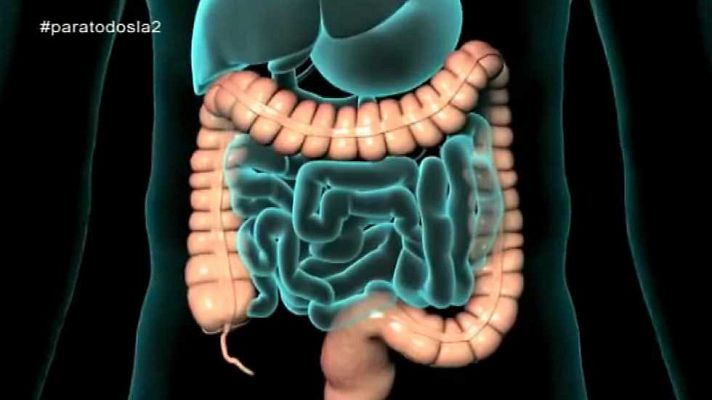

El cáncer de colon va en aumento. Es el segundo en mujeres y el tercero en hombres. La importancia de prevenir y detectarlo precozmente. Reportaje...

El cáncer de colon va en aumento. Es el segundo en mujeres y el tercero en hombres. La importancia de prevenir y detectarlo precozmente. Reportaje y coloquio con Isabel Portillo, coordinadora del programa de cáncer colorrectal en Euskadi y Fernando Carballo, médico del aparato digestivo del hospital Virgen de la Arrixaca de Murcia.